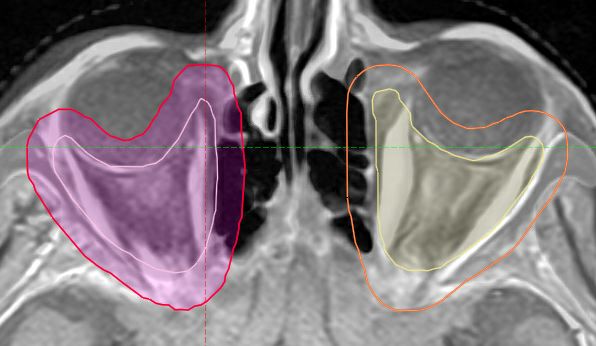

Zielvolumen Die Augenmuskeln sind das primäre Ziel bei der Strahlentherapie. Hier wurde ein Sicherheitssaum von 5 mm gewählt. ZV Orbitopathie Das Zielvolumen reicht bis zur Orbit der Spitze. ZV Orbita

ZV Orbita